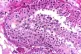

New research into mutations in sperm helps us better understand why they occur, while debunking a few myths in the process, write ROX MIDDLETON, LIAM SHAW and MIRIAM GAUNTLETT